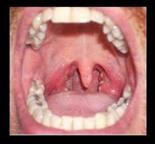

التعامل مع هذا النوع من السرطانات؟ إليك أهم المعلومات حول سرطان الحلق.

هذه بعض التفاصيل والمعلومات الهامة بخصوص أعراض سرطان الحلق وبعض المعلومات الهامة الأخرى التابعة له:

أعراض سرطان الحلق

قد تكون أعراض هذا النوع من السرطان صعبة التمييز في المراحل الأولى من المرض بينما تكون أكثر وضوحًا في المراحل المتأخرة، ولكن هذه هي قائمة أهم أعراض سرطان الحلق التي قد تظهر على البعض بشكل عام: